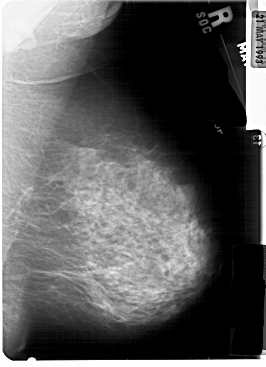

A_1834_1.RIGHT_MLO

RIGHT_CC LINES 5401 PIXELS_PER_LINE 3526 BITS_PER_PIXEL 12 RESOLUTION 43.5 NON_OVERLAY

FILE: A_1834_1.LEFT_CC.OVERLAY

TOTAL_ABNORMALITIES 1

ABNORMALITY 1

LESION_TYPE MASS SHAPE LOBULATED MARGINS OBSCURED

ASSESSMENT 4

SUBTLETY 4

PATHOLOGY BENIGN

TOTAL_OUTLINES 1

BOUNDARY